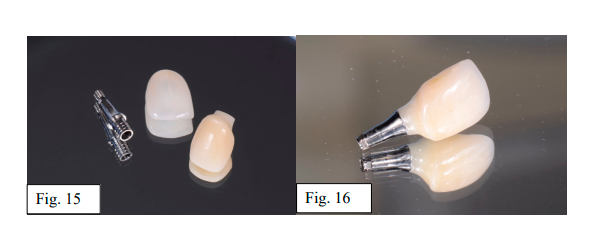

Após a etapa laboratorial concluída, foi realizada a cimentação da infraestrutura sobre o pilar Digital Implacil CM (3.8 x 3.5mm altura) com técnicas padrão recomendadas no tratamento do pilar e interior da infraestrutura com jateamento Al2O3 e uso de alloy primer + adesivo + cimentação resinosa Relyx U-200 (3M). Em seguida, após avaliação cromática com diferentes opções de cor, foi realizada a cimentação da faceta na estrutura com resina termo modificada fora da boca (fig. 15 e 16).